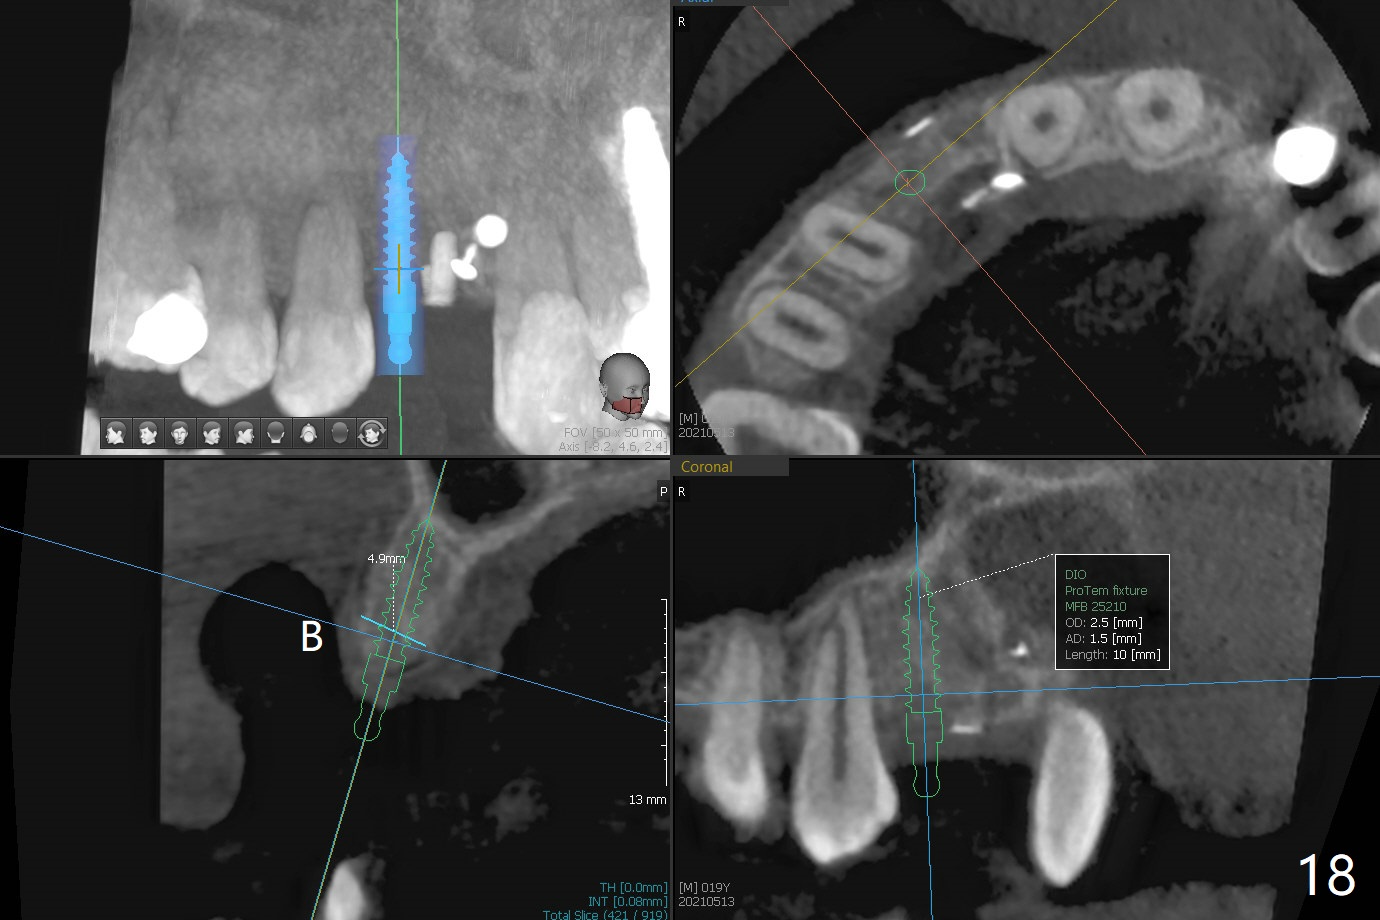

18岁男从外州大学回来,无症状,但是6号牙(右上尖牙)颊侧瘘道(图一,二(角化龈充分(箭头))),根尖片显示植体近中骨吸收(图三:*),而对侧植体仿佛骨整合(图四)。患侧切开后发现植体颊侧暴露,松动。拔除后骨缺损由粘性骨粉修复(图七,九:*),覆盖PRF膜(图七:P)和带钛网(图九:^)不可吸收膜(图五-七),后者用两个小钉子固定(图六(腭侧),七(颊侧),九),使用新的刀片和一个特殊尖头剥离器在颊侧骨膜下相当广泛分离,使用PTFE缝线,粘膜下水平褥式缝合之后(图八:箭头),多个垂直间断缝合,两个乳头垂直褥式缝合。术后一周伤口没有裂开,术后疼痛肿胀已经消退(图十)。术后十八天牙槽嵴仿佛比对侧还要宽(图十一,三与图十二,四(取模)对比)。术后5.5个月伤口没有裂开,牙槽骨,角化龈宽(图十六),与钛网和两个小钉子固定有关(图十五,十七)。CT显示牙槽骨只能容纳2.5或者3.0毫米植体(图十八)。11号牙植体牙冠粘固后没有骨质吸收(图十九),其实10,11号牙颊侧骨板隆起(图二十至二十二),而6植体失败,颊侧骨板吸收,甚至累及5号牙(图十七)。